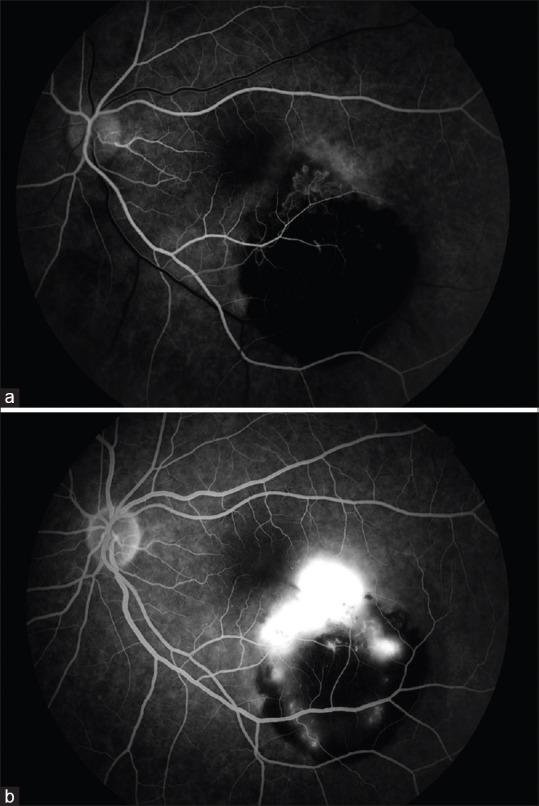

We reported a case of congenital hypertrophy of the retinal pigment epithelium (CHRPE) complicated by choroidal neovascular membrane (CNVM). A 41-year-old woman presented to our clinic with visual loss in the left eye. She was diagnosed as CHRPE complicated by a CNVM. The patient was treated with 2 consecutive monthly intravitreal aflibercept (IVA) injections. The best-corrected visual acuity (BCVA) improved and stabilized at 6/6. Subretinal fluid depending on CNVM resolved completely. CHRPE complicated by CNVM in the macular area is a rare condition and these cases can be treated with IVA therapy.

我们报告了一例先天性视网膜色素上皮肥大(CHRPE)合并脉络膜新生血管膜(CNVM)的病例。一名41岁女性因左眼视力丧失前来我院就诊。她被诊断为CHRPE合并CNVM。该患者接受了连续两个月每月一次的玻璃体内注射阿柏西普(IVA)治疗。最佳矫正视力(BCVA)提高并稳定在6/6。依赖于CNVM的视网膜下液完全消退。黄斑区CHRPE合并CNVM是一种罕见情况,这些病例可采用IVA疗法治疗。